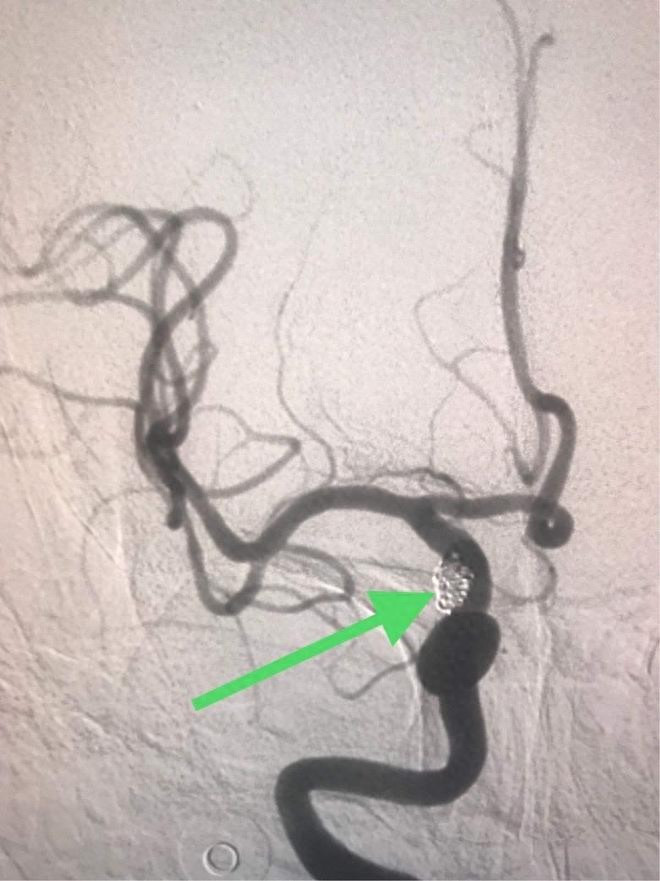

高风险斑块(重度狭窄或症状性斑块):可能需要更积极的治疗,包括强化药物治疗,甚至考虑手术干预(如颈动脉内膜剥脱术或支架植入术)。